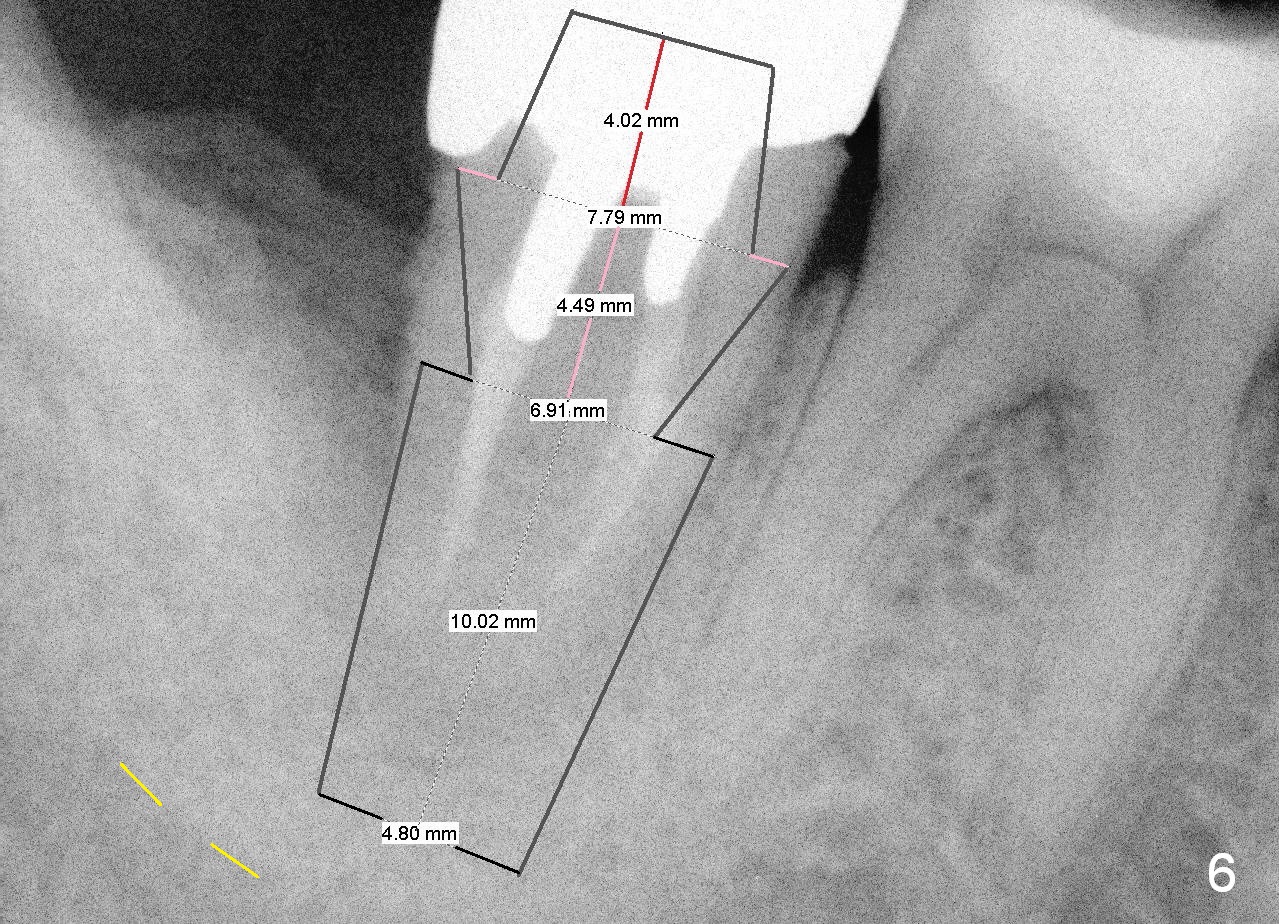

A 44-year-old man has had an asymptomatic distal defect of the tooth #31 for 8 years (Fig.1-5). Recently there is an acute episode of swelling and pain. A fistula develops mesiobucally. Panoramic X-ray films tend to show that the distal defect is deep (Fig.2,5; yellow dashed line: upper border of the Inferior Alveolar Canal). In addition, the distal defect may be not even buccolingually, as indicated by white and red arrowheads in Fig.3,4. Following placement of a 6.9x10 mm bone-level implant, a 7.8x4 (4.5) mm cemented abutment is inserted for try in (Fig.6). When it is fit, it is removed and a cover screw is temporarily placed. A piece of Osteotape (~10x4 mm) is placed distobuccally or distolingually (depending upon which wall is lower). A small amount of bone graft is packed between the most coronal portion of the implant and the Osteotape. The cover screw is then removed and the abutment is re-inserted and tightened by hand. An immediate provisional is fabricated with well-trimmed margin. Reline is done if necessary for securely holding bone graft in place. A new PA is to be taken prior to surgery to determine the extent of the lesion. Photos are taken to show the mesiobuccal fistula. Return to Lower Molar Immediate Implant Xin Wei, DDS, PhD, MS 1st edition 04/12/2015, last revision 05/25/2018